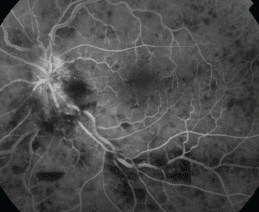

An eye doctor can also determine potential damage caused by CRVO by performing a test called fluorescein angiography. During this test, a dye is injected into the arm that “lights up” the blood vessels in the eye while multiple photos are taken of the back of the eye. This type of photography provides a clear picture of the retinal blood vessels for diagnosis. Additional tests may include imaging to determine the extent of swelling in the macula.

Fluorescein Angiography